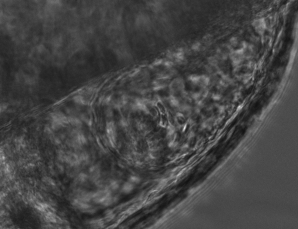

However, throughout development the zebrafish heart changes in size, shape and beat rate, causing difference between live brightfield images and the original reference heartbeat. These differences lead to errors in the prospective optical gating that will get ever larger when capturing over long, developmental time periods (fig. 1).

The combination of prospective optical gating for real-time phase matching and prospective optical gating for long-term phase locking allow us to capture in phase images over extended periods of times. Figure 4 demonstrates this phase locking over 18+ hours across a key developmental phase - heart looping.